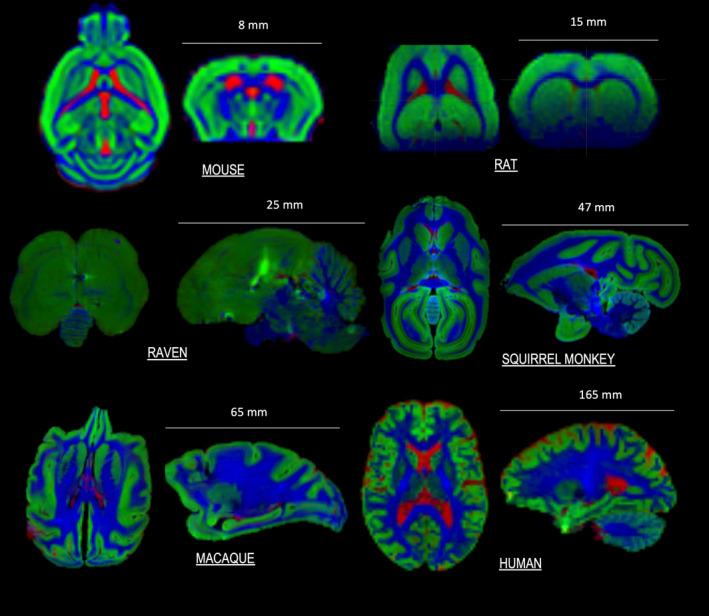

Small-animal diffusion MRI (dMRI) has been used for methodological development and validation, characterizing the biological basis of diffusion phenomena, and comparative anatomy. The steps from animal setup and monitoring, to acquisition, analysis, and interpretation are complex, with many decisions that may ultimately affect what questions can be answered using the resultant data. This work aims to present selected considerations and recommendations from the diffusion community on best practices for preclinical dMRI of in vivo animals. We describe the general considerations and foundational knowledge that must be considered when designing experiments. We briefly describe differences in animal species and disease models and discuss why some may be more or less appropriate for different studies. We, then, give recommendations for in vivo acquisition protocols, including decisions on hardware, animal preparation, and imaging sequences, followed by advice for data processing including preprocessing, model-fitting, and tractography. Finally, we provide an online resource that lists publicly available preclinical dMRI datasets and software packages to promote responsible and reproducible research. In each section, we attempt to provide guides and recommendations, but also highlight areas for which no guidelines exist (and why), and where future work should focus. Although we mainly cover the central nervous system (on which most preclinical dMRI studies are focused), we also provide, where possible and applicable, recommendations for other organs of interest. An overarching goal is to enhance the rigor and reproducibility of small animal dMRI acquisitions and analyses, and thereby advance biomedical knowledge.

小动物扩散磁共振成像(dMRI)已被用于方法学的开发与验证、表征扩散现象的生物学基础以及比较解剖学研究。从动物准备与监测到数据采集、分析和解读的各个步骤都很复杂,存在许多决策,这些决策最终可能会影响利用所得数据能够回答哪些问题。这项工作旨在介绍扩散领域关于体内动物临床前dMRI最佳实践的一些选定考量因素和建议。我们描述了设计实验时必须考虑的一般考量因素和基础知识。我们简要描述了动物物种和疾病模型的差异,并讨论了为什么有些可能更适合或不太适合不同的研究。然后,我们给出了体内采集方案的建议,包括硬件、动物准备和成像序列的决策,接着是数据处理的建议,包括预处理、模型拟合和纤维束成像。最后,我们提供了一个在线资源,列出了公开可用的临床前dMRI数据集和软件包,以促进负责任和可重复的研究。在每个部分,我们都试图提供指导和建议,但也强调了尚无指南的领域(以及原因),以及未来工作应关注的方向。虽然我们主要涵盖中枢神经系统(大多数临床前dMRI研究都聚焦于此),但在可能且适用的情况下,我们也为其他感兴趣的器官提供了建议。一个总体目标是提高小动物dMRI采集和分析的严谨性和可重复性,从而推动生物医学知识的进步。